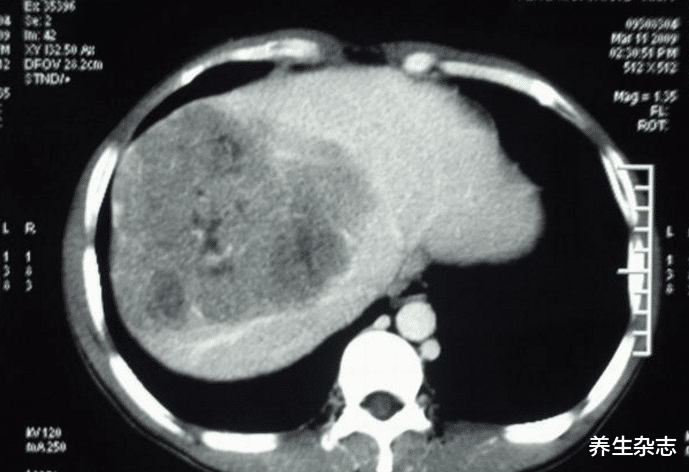

医生询问了张老师的基本情况后 , 直接安排她进行了肝部的检查 。 不曾想出来的检查结果直接让张老师崩溃了 。 她体内的甲胎蛋白数值已经达到了490mg/ml , 肝脏内出现了多个肿瘤 , 最终被确诊为肝癌 。 张老师思考了很久都没有想明白 。 自己为什么会得了这么严重的肝病?

判断肝脏受损的指标——甲胎蛋白数值

【肝癌|47岁女教师确诊肝癌,医生叹息:糊涂!鸡蛋和它一起煮,等同于“吃毒”】在临床上 , 甲胎蛋白指数往往与肝脏肿瘤有着密切的联系 , 像是很多原发性肝癌就会使得甲胎蛋白出现明显的增高 , 其数值往往是大于300mg/ml的 。 成人在患上肝脏疾病时 , 体内的甲胎蛋白就会出现十倍甚至几十倍的攀升 。